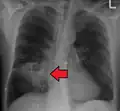

Lung abscesses are often on one side and single involving posterior segments of the upper lobes and the apical segments of the lower lobes as these areas are gravity dependent when lying down. Presence of air-fluid levels implies rupture into the bronchial tree or rarely growth of gas forming organism.